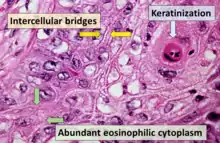

_squamous_cell_carcinoma_histopathology.jpg.webp)

Medical history, physical examination and medical imaging may suggest a squamous cell carcinoma, but a biopsy for histopathology generally establishes the diagnosis. TP63 staining is the main histological marker for Squamous cell carcinoma. In addition, TP63 is an essential transcription factor to establish squamous cell identity.[12]

Cancer can be considered a very large and exceptionally heterogeneous family of malignant diseases, with squamous cell carcinomas comprising one of the largest subsets.[13][14][15] All SCC lesions are thought to begin via the repeated, uncontrolled division of cancer stem cells of epithelial lineage or characteristics. SCCs arise from squamous cells, which are flat cells that line many areas of the body. Some of which are keratinocytes. Accumulation of these cancer cells causes a microscopic focus of abnormal cells that are, at least initially, locally confined within the specific tissue in which the progenitor cell resided. This condition is called squamous cell carcinoma in situ, and it is diagnosed when the tumor has not yet penetrated the basement membrane or other delimiting structure to invade adjacent tissues. Once the lesion has grown and progressed to the point where it has breached, penetrated, and infiltrated adjacent structures, it is referred to as "invasive" squamous cell carcinoma. Once a carcinoma becomes invasive, it is able to spread to other organs and cause the formation of a metastasis, or "secondary tumor".